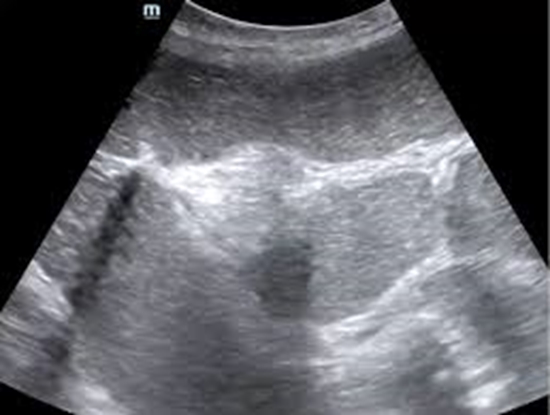

بررسی correlation یافته های سونوگرافی روده در کودکان شناخته شده یا مشکوک به ابتلا به بیماریIBD بین سنین 6 تا 18 سال در مقایسه با MRE انها در مراجعه کنندگان به بخش رادیولوژی بیمارستان مرکز طبی اطفال در سال های 1398/1399

سونوگرافی روده در کودکان شناخته شده یا مشکوک به ابتلا به بیماریIBD